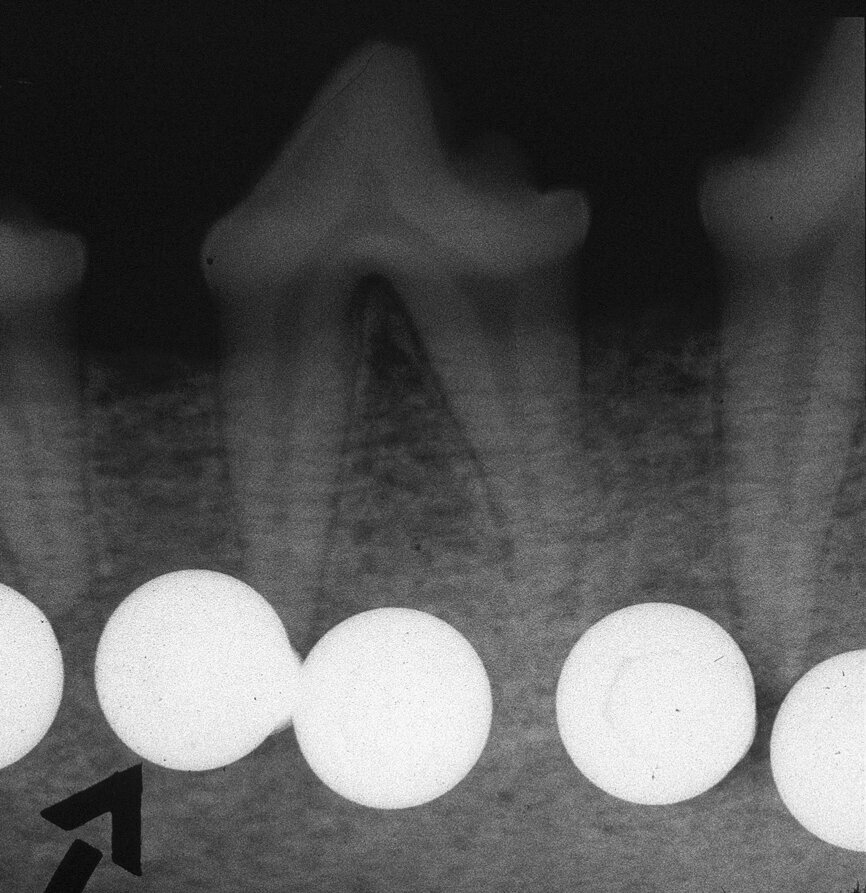

Fig. 1 : Radiographie panoramique. Il faut noter l’espace restreint en position de la dent 22.

Une jeune femme de 21 ans, en bonne santé, nous a consultés pour un problème d’agénésie de l’incisive latérale gauche maxillaire. Elle avait suivi un traitement orthodontique durant trois ans au bout duquel l’orthodontiste n’avait pu obtenir qu’un espace mésio-distal de 4 mm entre le point de contact mésial de la canine supérieure gauche et le point de contact distal de l’incisive centrale gauche maxillaire. L’analyse de la radiographie périapicale numérique a montré qu’au-delà des six premiers millimètres sous le niveau de l’os crestal, 2,7 mm seulement séparaient les racines des deux dents, et après 8 mm, la distance n’était plus que de 2,1 mm (Fig. 2). Nous avons conseillé un second traitement orthodontique à la patiente, mais elle a refusé et nous avons donc discuté de la pose d’un implant étroit par la technique d’ouverture de l’espace inter-radiculaire. L’implant avait un diamètre de 3 mm, une longueur de suivantes : implant Press-Fit inséré dans l’ostéotomie ; design en plateau sans filetage ; épaulement incliné assurant un diamètre inférieur au niveau du col (selon le concept dit du « platform-switching ») ; positionnement sous-crestal à 1–3 mm sous le niveau de l’os crestal. La patiente a été anesthésiée par une injection d’articaïne et d’épinéphrine (Septocaïne, Septodont), et une légère incision crestale au moyen d’une lame de bistouri de 15c a été réalisée. Le foret-guide a été utilisé à une vitesse de rotation de 1 100 tr/min afin de perforer l’os cortical jusqu’à une profondeur approximative de 4 mm. Un alésoir manuel de Ø 2,5 mm puis un second de Ø 3 mm ont été utilisés pour effectuer pour ouvrir l’espace entre les racines.3, 4